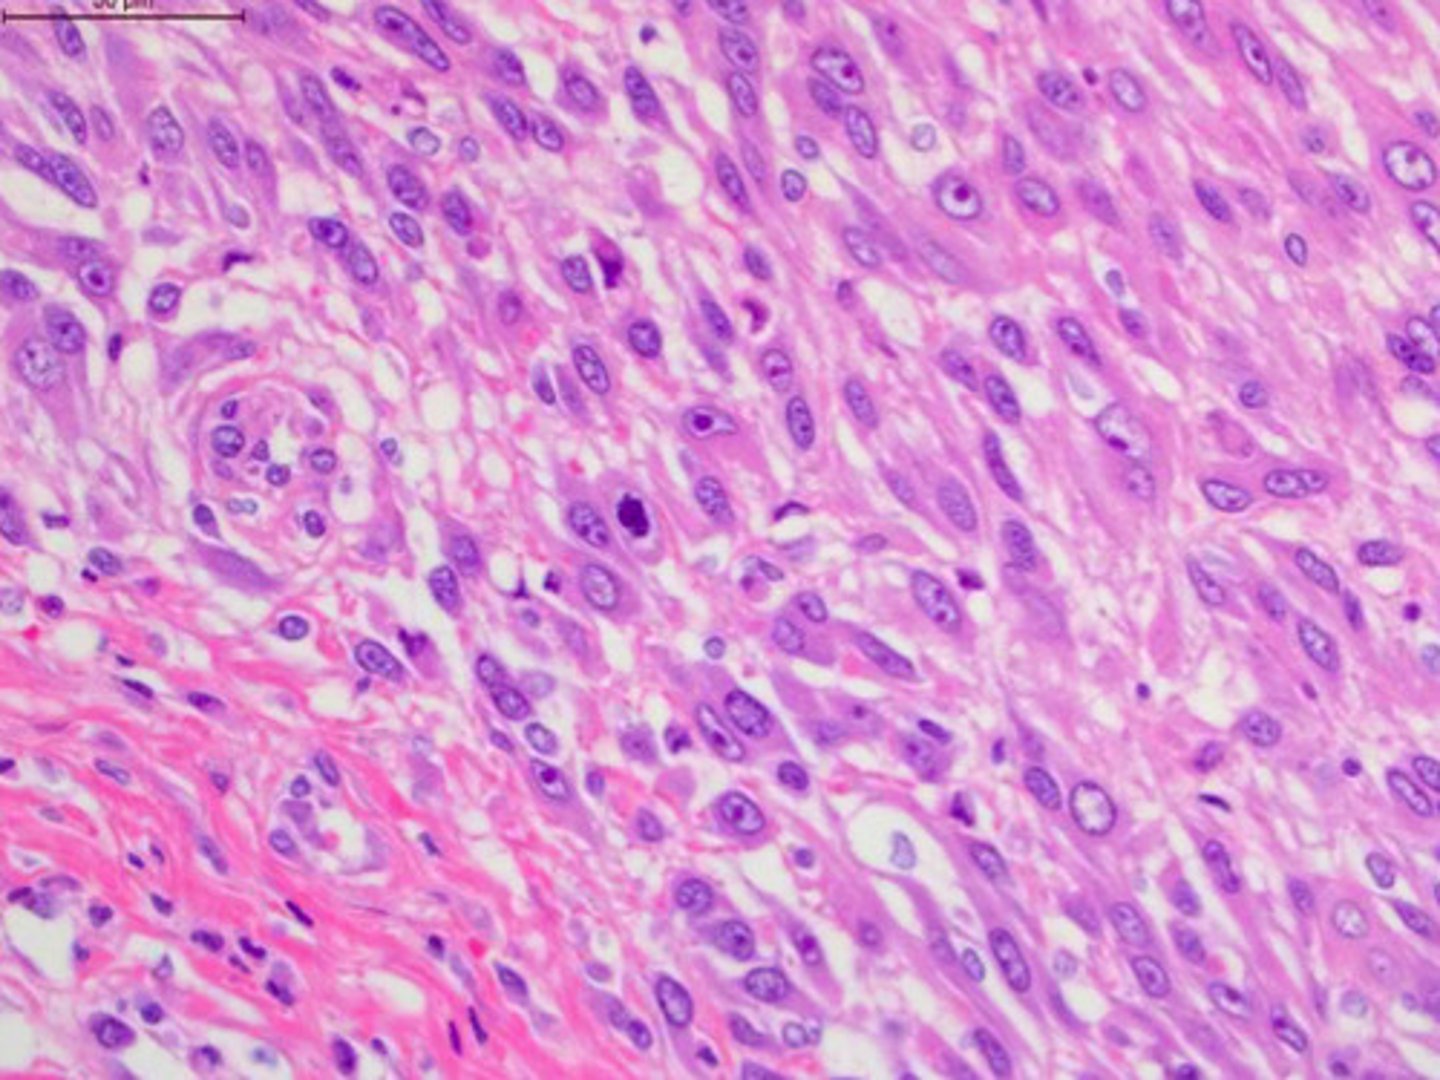

Identify the pathology:

Osteosarcoma -